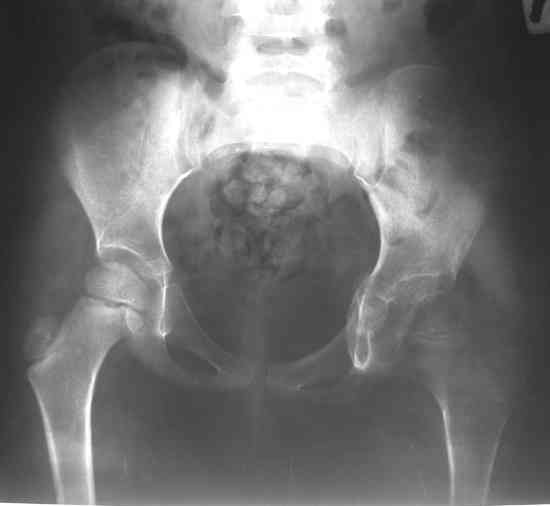

Уважаемые коллеги! Девочка, 5 лет. Диагноз: Остеохондрома левого тазобедренного сустава. Поступила 23.07.07. с жалобами на боли и ограничения движений в левом тазобедренном суставе. Болеет около года, в 2006 г. проходила стац.лечение с диагнозом левосторонняя коксалгия неясного генеза. 26.07.07. - операция: удаление новообразования левого тазобедренного сустава <Под общим обезболиванием произведена 3-х кратная обработка операционного поля бетадином, произведен разрез в области большого вертела левого бедра до 10 см. Тупо и остро выделен левый тазобедренный сустав. Гемостаз по ходу разреза. Рана промыта растворами антисептиков. В области левого тазобедренного сустава (вертлужная впадина) обнаружено новообразование хрящевой консистенции. Долотом, электроножом и ложкой Фолькмана новообразование максимально удалено. Дефект подвздошной кости заполнен <Тутопластом>. Мягкие ткани послойно ушиты. Дренаж, ас.повязка. Гонитная гипсовая повязка.>

На первом снимке таза (до операции?)имеется протрузия левой вертлужной впадины, бедро оттеснено кнаружи и головка его деформирована, на уровне верлужной ямки определяется выбухание кости. остеопороз бедренной кости без ее атрофии. массивный отек окружающих периартикулярных мягких тканей.

Складывается впечатление о каком-то длительно существующем мягкотканном образовании в области дна вертлужной впадины - хондроме?хондроматозе?.

Для рентген-негативного хондроматоза не хватает краевых вдавлений на головке и шейке бедра, и описания такой протрузии вертлужной впадины при хондроматозе я в литературе не нашел.